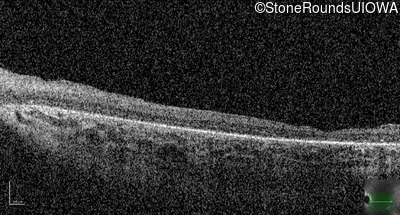

Age at visit: 10 years

OD OS

Age at visit: 11 years

Age at visit: 12 years

Age at visit: 13 years

Age at visit: 14 years

Age at visit: 16 years